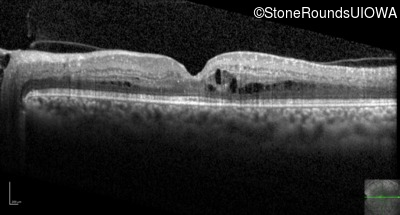

Optical Coherence Tomography - Left - 20/25 -3

Exemplar / OCT Stack

OCT Stack